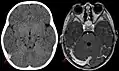

Синус-тромбоз при нативной компьютерной томографии (слева) и МРТ в режиме T1 с контрастным усилением (справа)